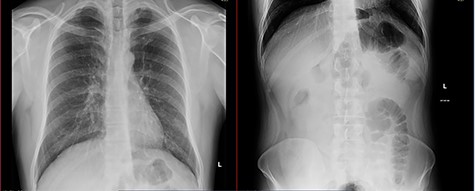

A 38-year-old male patient with neither known medical history nor former abdominal surgery was admitted to the emergency department with a 5-day history of abdominal pain associated with vomiting. He was hemodynamically stable and apyretic. The abdomen was moderately distended. Routine blood tests revealed only a mild electrolyte imbalance. Plain abdominal X-ray demonstrated a gastrectasia without significant bowel air-fluid levels (Fig. 1). A routine nasopharyngeal swab to detect SARS-CoV-2 infection with molecular real-time polymerase chain reaction test resulted positive. No respiratory symptoms or anomalies were discovered. The symptoms were referred to a gastroenteritis COVID-19 related and the patient was admitted to the Infectious Disease Hospital.